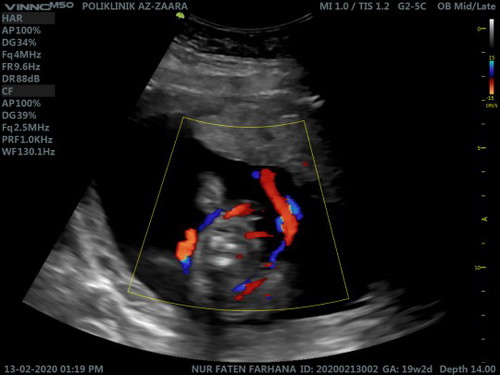

Tali pusat berpusing

Hi mummies. nak tanya. saya scan ritu details 19weeks. now 22 weeks alhamdulillah. tapi, based on gambar doc kata tali pusat mcm kat keliling badan dia. baru 1 pusing. tp doc kata insyaallah takde apa2. sbb baby baru gerak2 main2. tapi sy risau huu. sape2 ada pengalaman? nak minta tips - hmm bak kata mak saya, bukan kita bole alihkan tali pusat tu ? minta doa baby saya sedang main2 tu je ye nanti normal la tu. tq semua